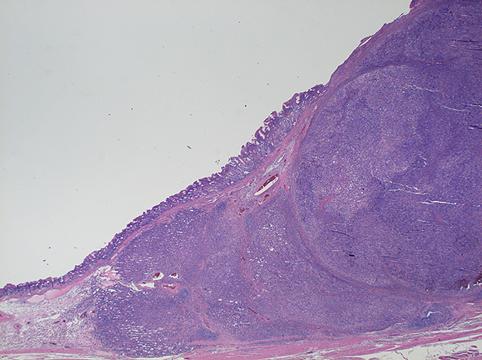

Criteria of Hist.ClassificationMalignant epithelial tumor/Adenocarcinoma

LocationStomach/Gastroesophageal junction

Macroscopic TypesType 2 Ulcerated type with clear margin/

Size40 -

Depth of Tumor Invasionsubserosa (subadventitia)